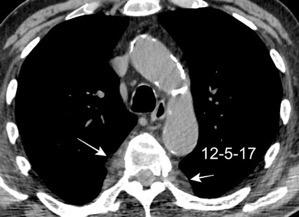

Signos radiológicos TC

Hallifax RJ et al. State-of-the-art: Radiological investigation of pleural disease Respiratory Medicine 2017

Nivel hidroaéreo o burbujas

Forma lenticular o elíptica Ángulos obtusos

> Grasa Extrapleural (60-80%)

Situación no gravitacional (no siempre)

Compresión de estructuras pulmonares

Límite muy bien definido Tabicación

Patrón ecográfico de empiema

Empiema

El derrame paraneumónico se convierte en complicado en 5-10% de los casos

Engrosamiento de la pleura parietal 36/ 59 exudados (61%) 56% de D. paraneumónicos 100% de empiemas Especificidad.. 96%.

Exudado versus trasudado.

Aquino SL, et al. Pleural exudates and transudates: diagnosis with contrast-enhanced CT. Radiology 1994

Signo de la Pleura separada “Split pleural sign”

Capas pleurales de grosor uniforme realzadas por el contraste

Dr. César Pedrosa

No específico de empiema. Indica “exudado”. 68% de pacientes con empiema pleural.

Capas pleurales de grosor uniforme

Realce grasa extrapleural (30%)

> Grasa Extrapleural. (60-80%)

Kraus GJ. Split pleural sign. Radiology 2007